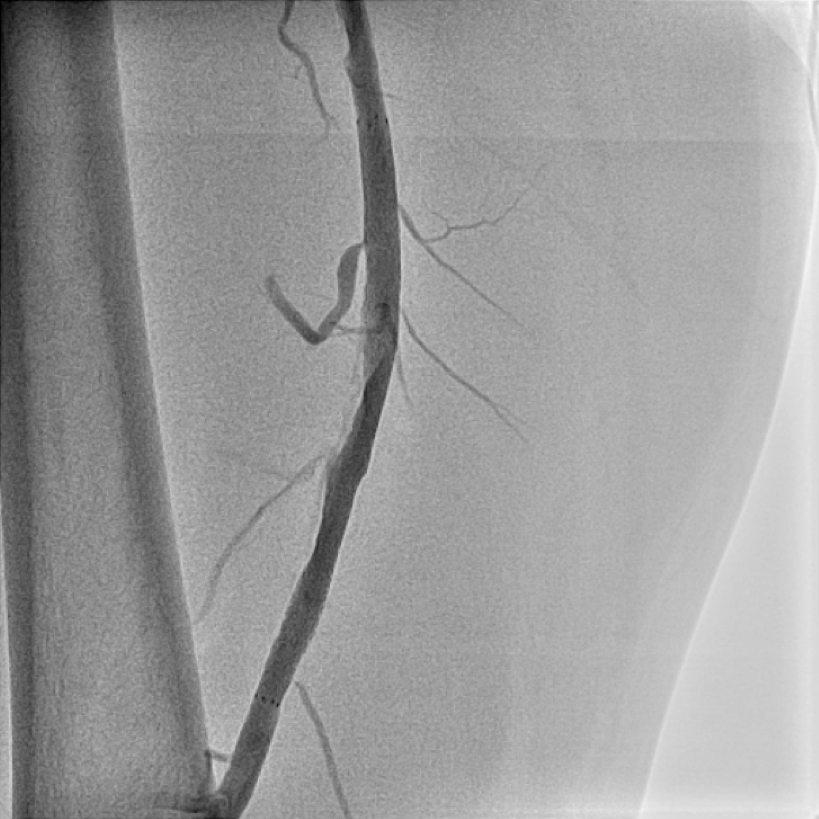

図6

カテーテル治療を行い、血流再開いたしました。